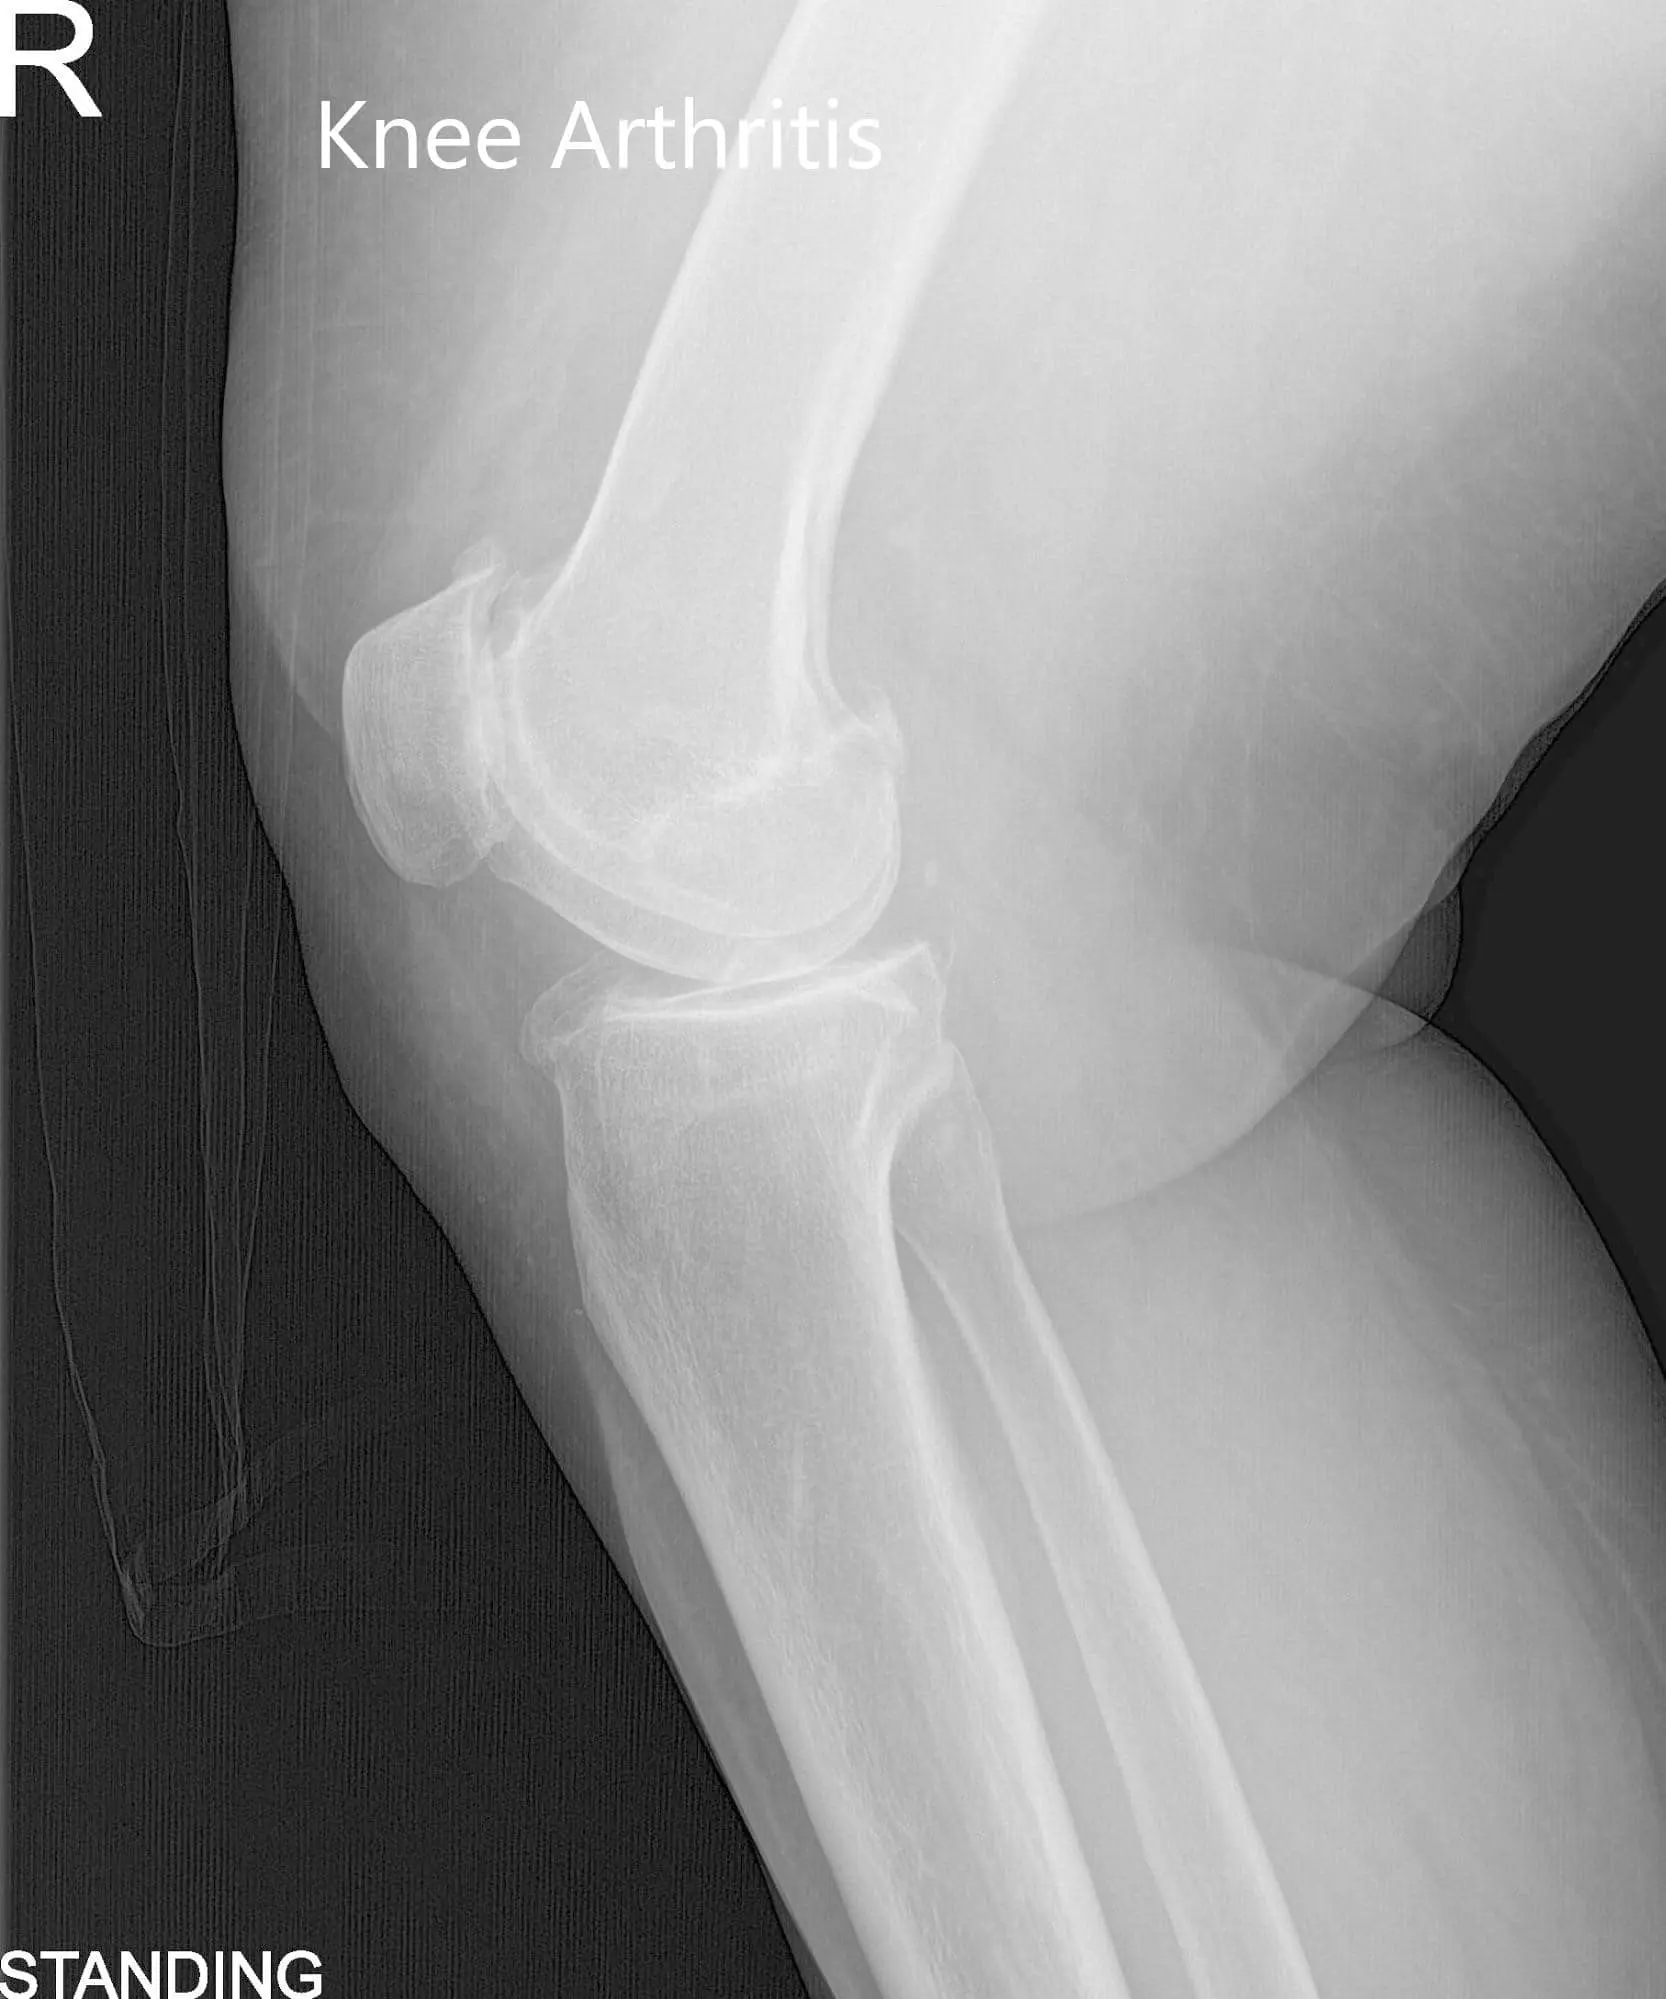

Physical examination revealed genu varus deformity and mildly swollen right knee joint. There was marked joint crepitus throughout the range of motion with moderate medial and lateral joint line tenderness and patellar facet tenderness. Imaging studies revealed marked narrowing of the medial joint compartment and patellofemoral joint compartment with moderate osteophyte formation.

Pre-Operative AP and Lateral X-Ray views of the right knee (standing)